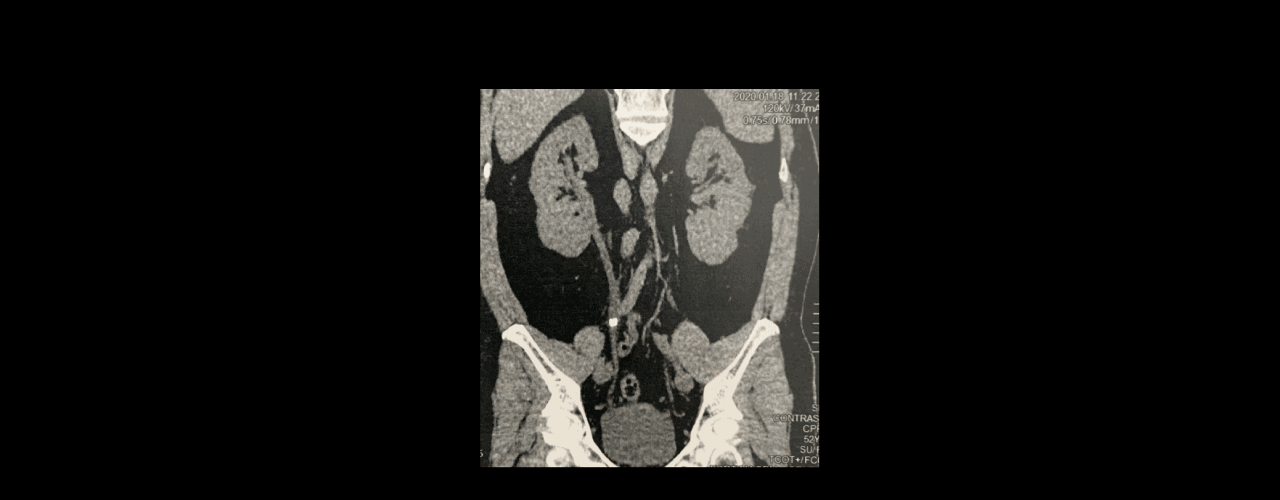

A Ureterorrenolitotripsia Laser é uma cirurgia realizada por dentro do canal urinário para tratar os cálculos renais.

É possível acessar os cálculos e fragmentar os cálculos através do Laser.